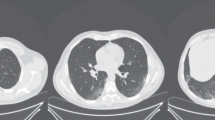

Lung Segmentation is one of the pre-processing steps for lung cancer diagnosis. Segmentation of lung contour is challenging when the nodules are attached to the surrounding tissues of the lung, such as juxta-pleural boundary or vasculature. This paper proposes a lung parenchyma segmentation framework based on multiple image frames with novel approaches for juxta-pleural nodule identification and lung contour correction. The juxta-pleural nodule identification works by computing the distance between the lung borders on adjacent slices. These approaches extract the lung boundary of current and previous slices and calculate the shortest distance between the two boundary contour points to detect the nodule candidates and correct the nodule boundary. These approaches were experimented on at least 11 thoracic image volumes with juxta-pleural nodules from the LIDC-IDRI dataset and achieved an average volumetric overlap fraction of 98.59%. Compared with the other state-of-the-art methods, the proposed method is simple and very efficient for segmenting the lung parenchyma while including the juxta-pleural nodules.